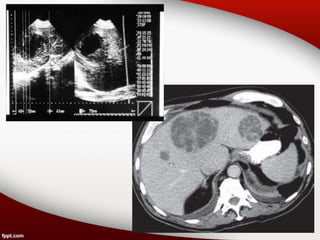

Hallazgos radiológicos

• ECOGRAFÍA: existen zonas hiperecógenas o

hipoecógenas heterogéneas mal definidas que

van tomando el aspecto de COLECCIÓN con

refuerzo posterior.

• TOMOGRAFÍA COMPUTADA: la lesión

hipodensa se halla rodeada por una envoltura

más o menos gruesa que se realza claramente